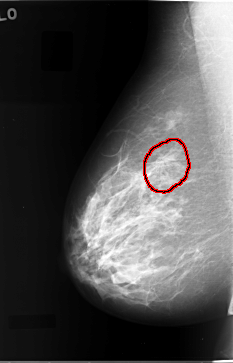

C_0032_1.RIGHT_MLO

RIGHT_MLO LINES 5808 PIXELS_PER_LINE 3720 BITS_PER_PIXEL 12 RESOLUTION 50 OVERLAY

FILE: C_0032_1.RIGHT_MLO.OVERLAY

TOTAL_ABNORMALITIES 1

ABNORMALITY 1

LESION_TYPE MASS SHAPE ARCHITECTURAL_DISTORTION MARGINS ILL_DEFINED

ASSESSMENT 4

SUBTLETY 2

PATHOLOGY MALIGNANT

TOTAL_OUTLINES 1

BOUNDARY